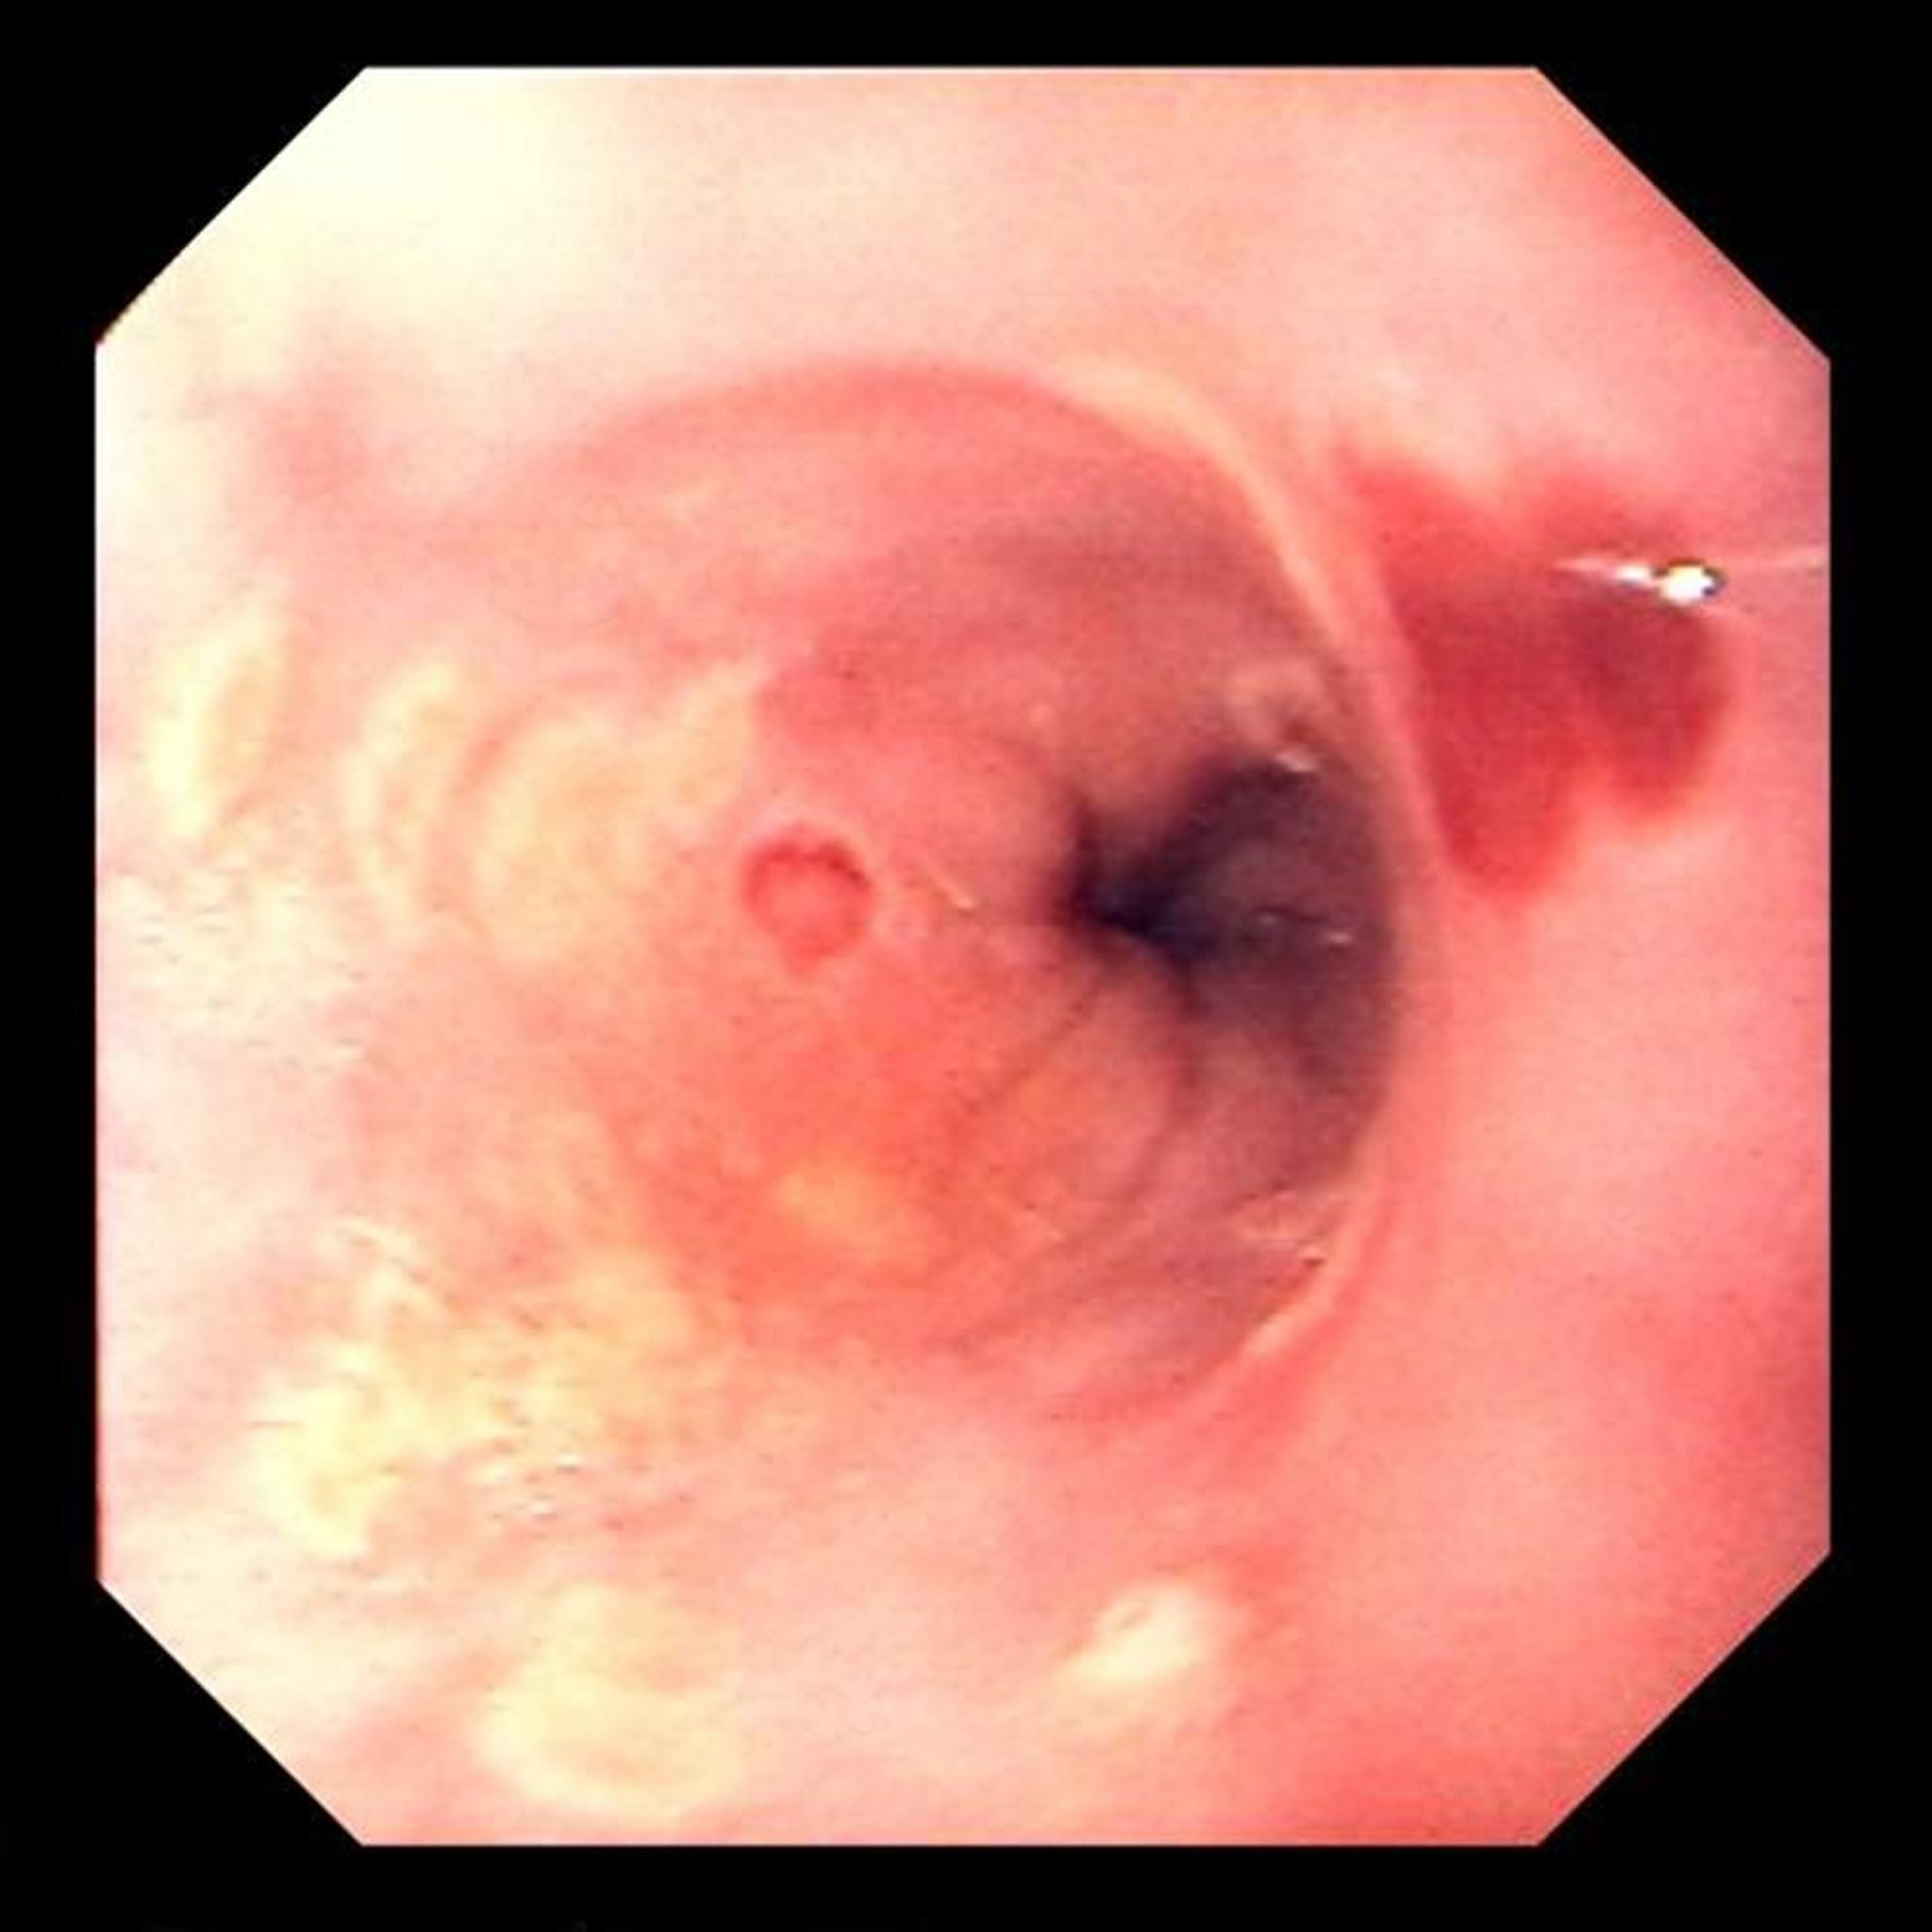

Esofagitis por herpes simple

Las ulceraciones focales son características de la esofagitis causada por el virus del herpes simple.

Image provided by David M. Martin, MD.